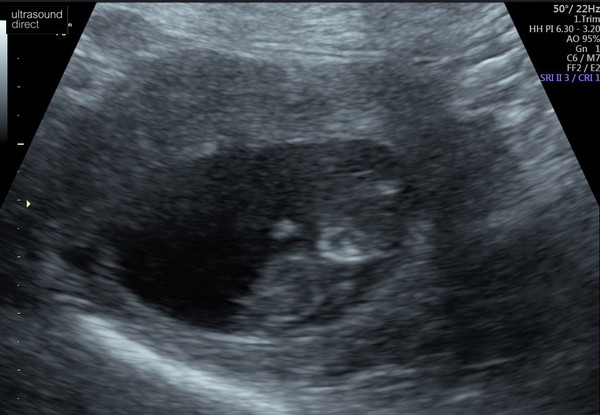

Ladies my heart is full, everything was perfect at the scan. I'm measuring 10+4 🥰

@vitaminb33 thank you, I've had a little cry. Just so happy and relieved. They have sent us lots of images and even some videos, can see the little heartbeat 💓

So glad to see @MrsTD88 ! I refreshed this thread not long ago and no replies came up so I’ve been panicking at your lack of response thinking something was wrong. Such a relief it was just a technical glitch. That’s a great photo too, you can really see them starting to form into a baby 😊 sure you feel great!